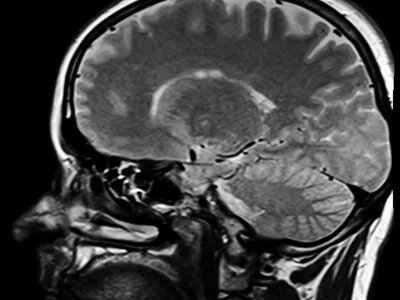

Ученые выяснили, как коронавирус SARS-CoV-2 поражает мозг